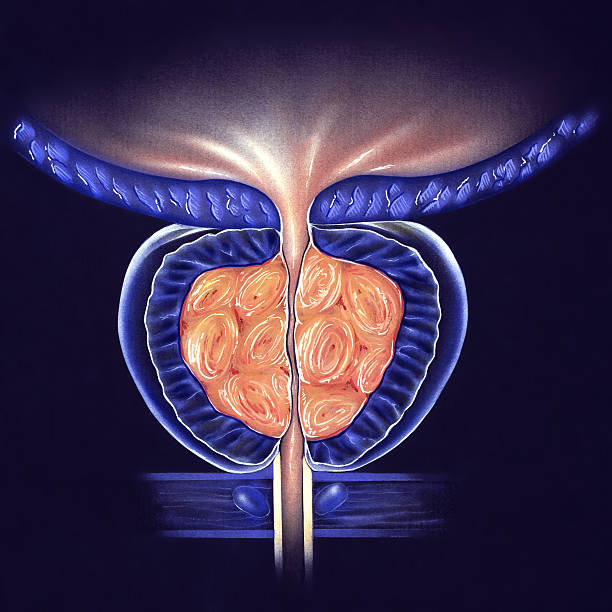

전립선비대증은 전립선의 세포가 비정상적으로 증식하면서 발생합니다. 이러한 세포 증식으로 인해 전립선이 커지면서 요도 주변을 압박하고, 배뇨와 관련된 증상을 유발합니다. 전립선비대증은 일반적으로 배뇨 불편, 방광염, 자주 병원가는 등의 증상을 유발합니다.

전립선 저적술은 전립선의 크기를 줄이는 방법 중 하나로, 저온열을 이용하여 전립선 조직을 소실시키는 방법입니다. 전립선 비대증의 정도에 따라 다양한 방법으로 시행됩니다.